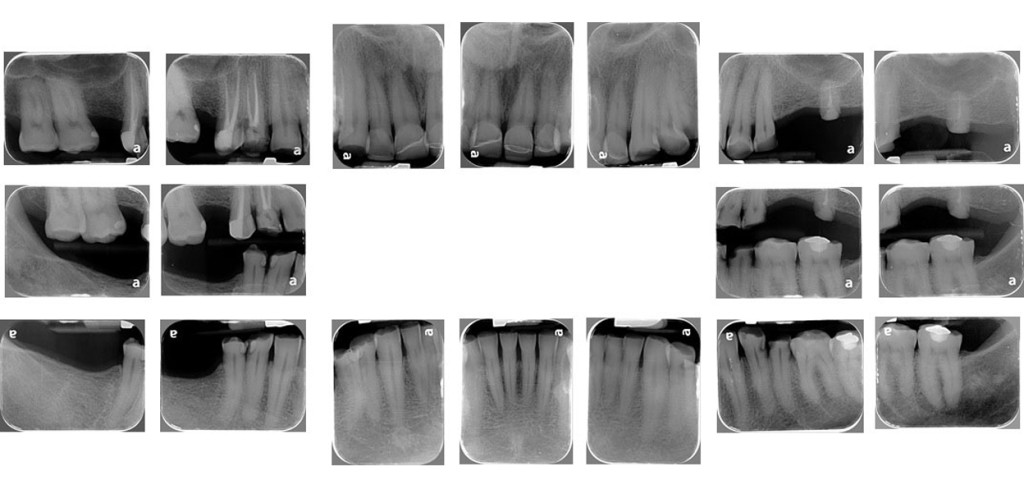

RADIOGRAFÍAS

PERIAPICALES SERIE

Te permite conocer a detalle el estado pulpar, radicular, periapical y de soporte de cada zona dental, es la visión clínica que complementa la valoración odontológica.